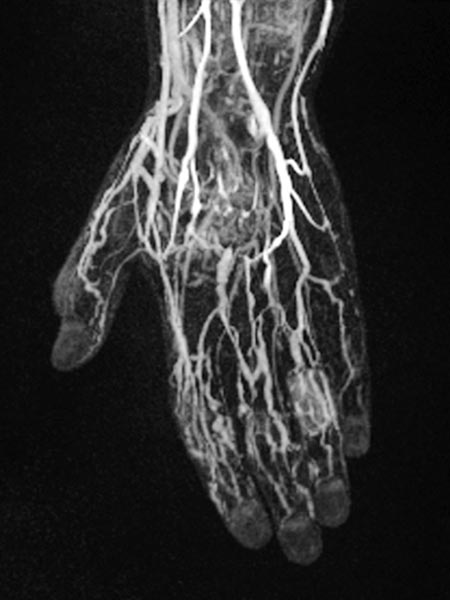

Dynamisch, kontrastmittelunterstützte MR-Angiographie der Hand, 30 s nach KM-Injektion intravenös.

Normale Handarterien, keine Fast-flow-Situation, keine erweiterten Arterien oder arteriovenöse Shunts.

Dynamisch, kontrastmittelunterstützte MR-Angiographie der Hand, 35 s nach KM-Injektion intravenös.

Bereits in dieser früharteriellen Phase erste Kontrastierung von Teilen der Malformation über kleine arteriovenöse Fisteln (AVF) vor allem an Daumen, Zeigefinger und Ringfinger.

Dynamisch, kontrastmittelunterstützte MR-Angiographie der Hand, 67 s nach KM-Injektion intravenös.

In dieser venösen Phase dann langsames geringes KM-Pooling innerhalb der venösen Malformation.